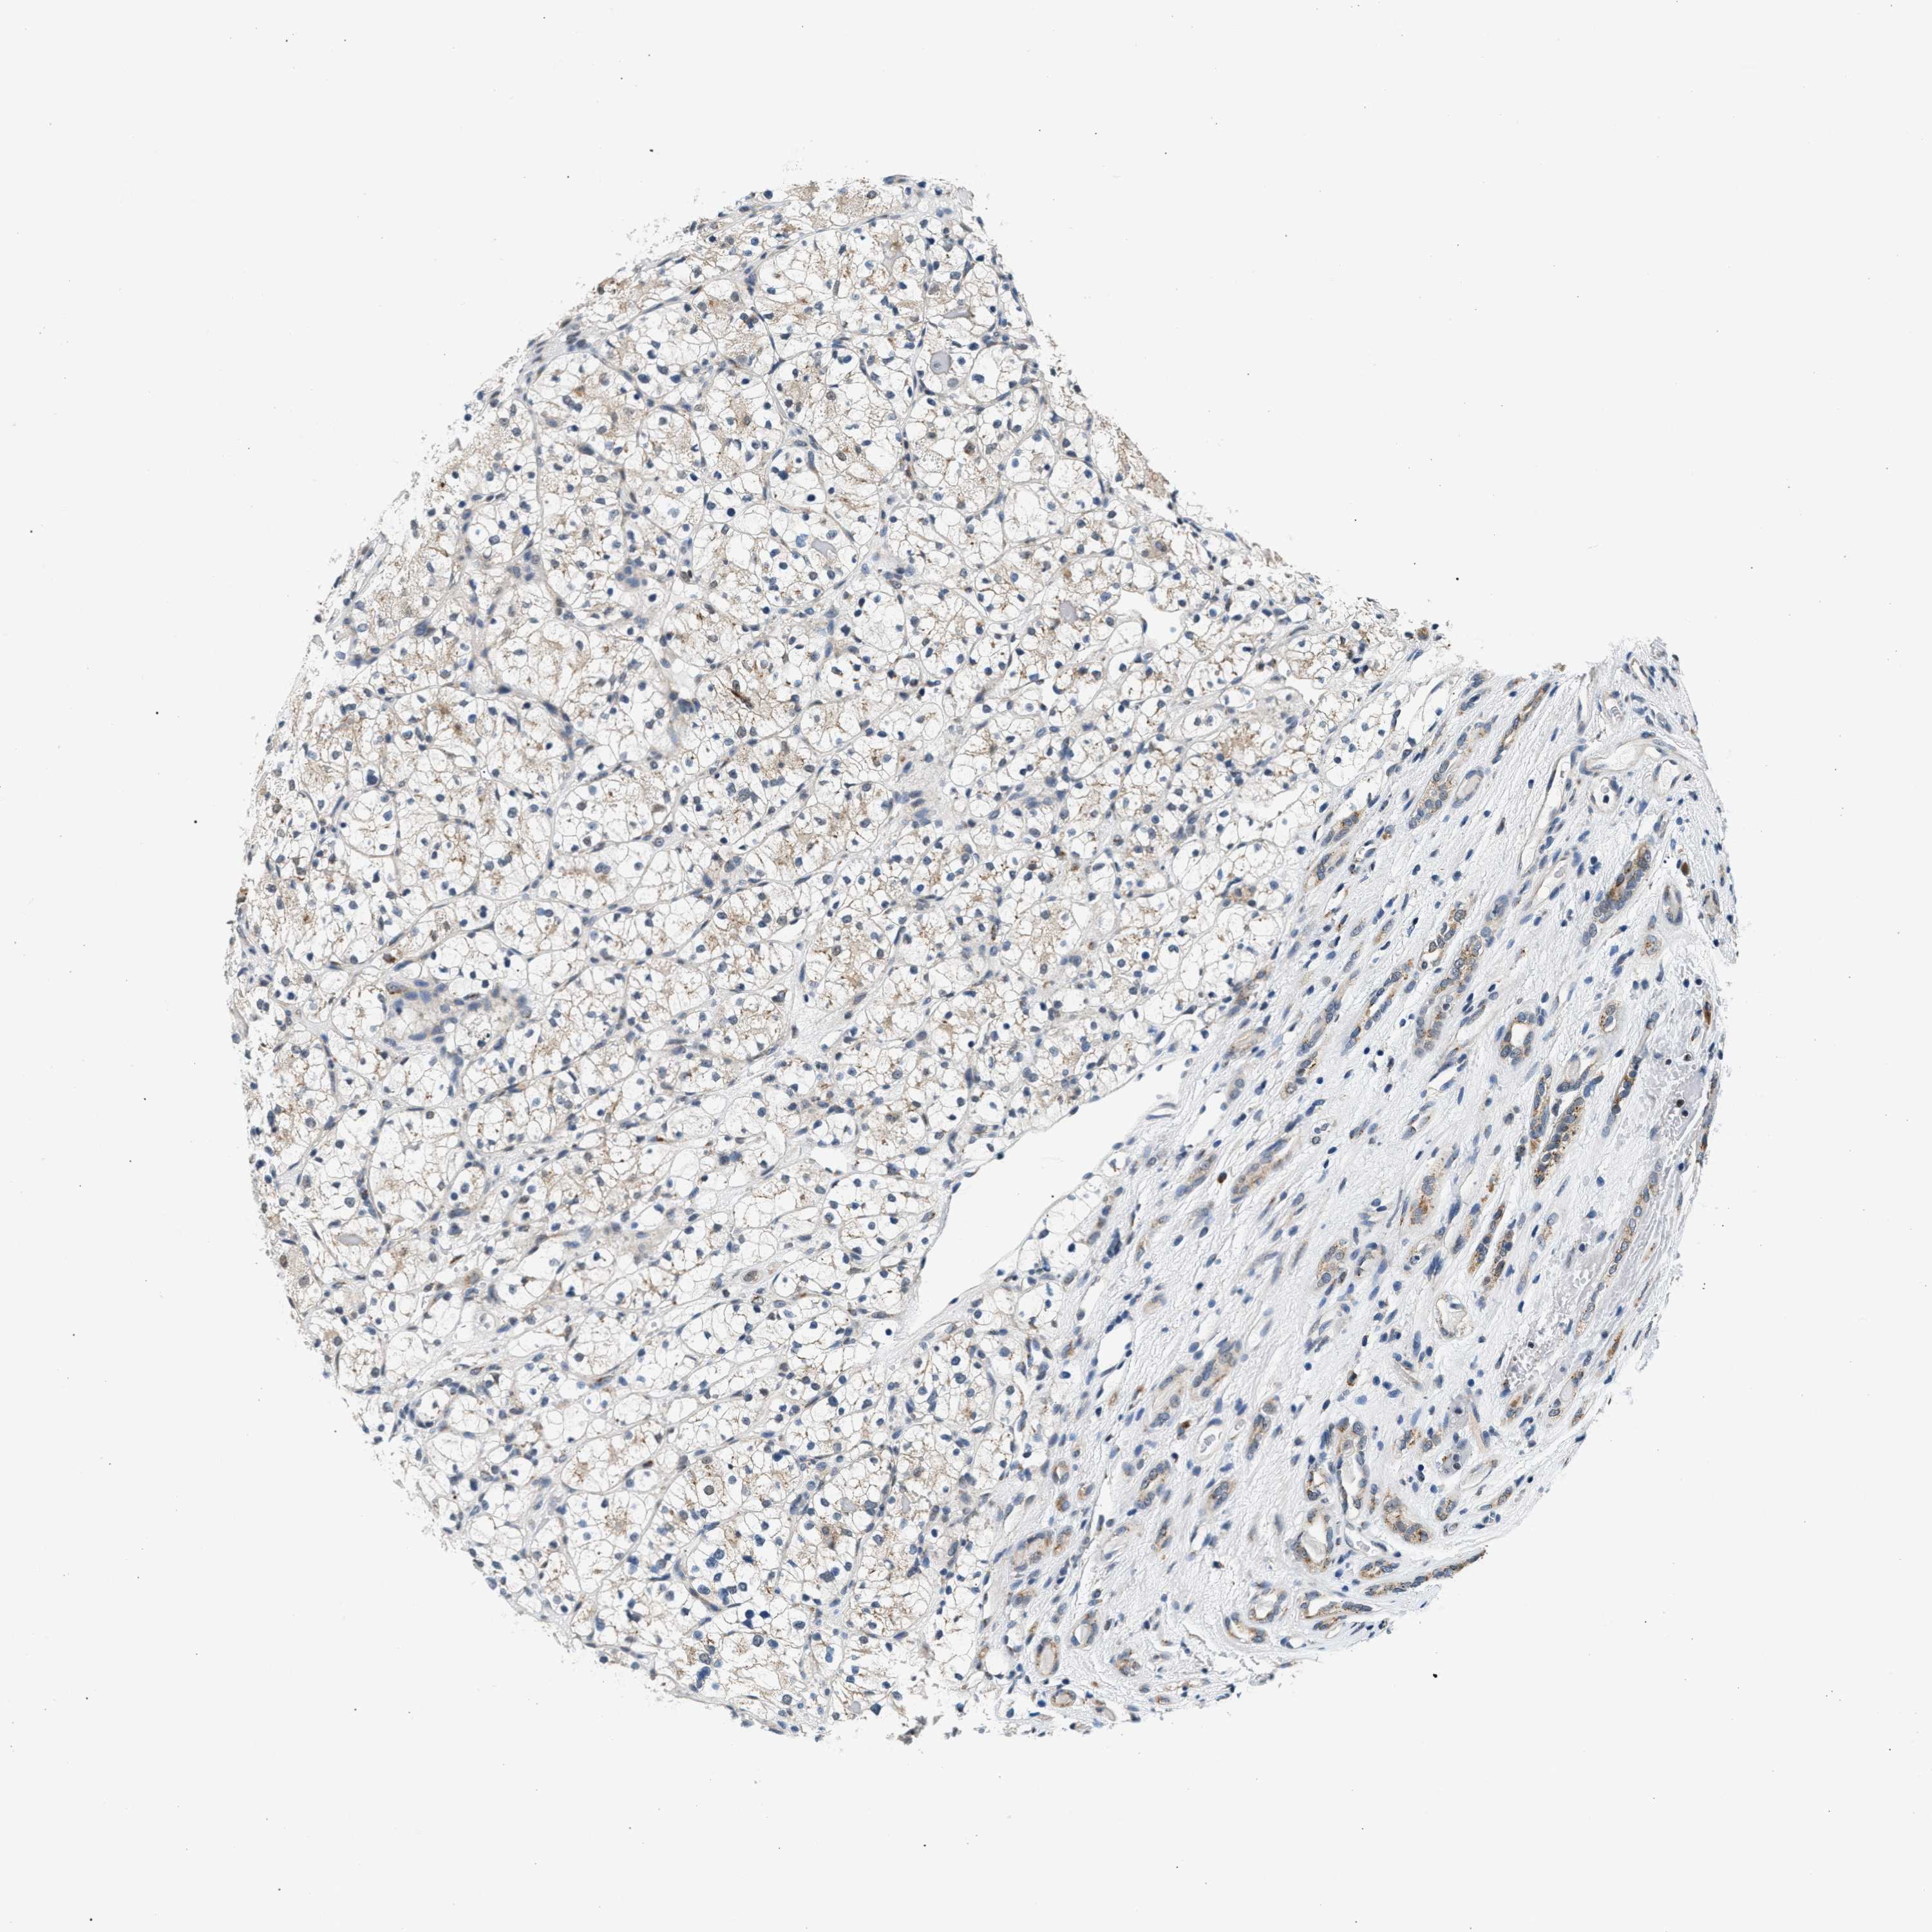

KIDNEY CHROMOPHOBE (TCGA) - Interactive survival scatter ploti

The Survival Scatter plot shows the clinical status (i.e. dead or alive) for all individuals in the patient cohort, based on the same data that underlies the corresponding Kaplan-Meier plots. Patients that are alive at last time for follow-up are shown in blue and patients who have died during the study are shown in red.

The x-axis shows the expression levels (FPKM) of the investigated gene in the tumor tissue at the time of diagnosis. The y-axis shows the follow-up time after diagnosis (years). Both axes are complimented with kernel density curves demonstrating the data density over the axes. The top density plot shows the expression levels (FPKM) distribution among dead (red) and alive patients (blue). The right density plot shows the data density of the survived years of dead patients with high and low expression levels respectively, stratified using the cutoff indicated by the vertical dashed line through the Survival Scatter plot. This cutoff is automatically defined based on the FPKM cutoff that minimizes the p-score. The cutoff can be changed by dragging the vertical line or by entering a cutoff value in the square labeled "Current cut-off".

Under the Survival Scatter plot the p-score landscape (black curve; left axis) is shown together with dead median separation (red curve; right axis). Dead median separation is the difference in median mRNA expression between patients who have died with high and low expression, respectively. It is calculated as follows: median FPKM expression of dead patients with high expression - median FPKM expression of dead patients with low expression. This is intended to aid the user in visually exploring custom cutoffs and the associated p-scores and dead median separation.

Individual patient data is displayed and can be filtered by clicking on one or more of the category buttons on the top of the page. Categories describing expression level and patient information include: high, low, alive, dead, female, male and tumor stages. The scale of the x-axis can be toggled between linear and log-scale by clicking on the "x log" button. Mouse-over function shows TCGA ID, patient information and mRNA expression (FPKM) for each patient.

& Survival analysisi

Kaplan-Meier plots summarize results from analysis of correlation between mRNA expression level and patient survival. Patients were divided based on level of expression into one of the two groups "low" (under cut off) or "high" (over cut off). X-axis shows time for survival (years) and y-axis shows the probability of survival, where 1.0 corresponds to 100 percent.

KCNMB2 is not prognostic in Kidney Chromophobe (TCGA)

Average pTPM 3.0

Number of samples 64